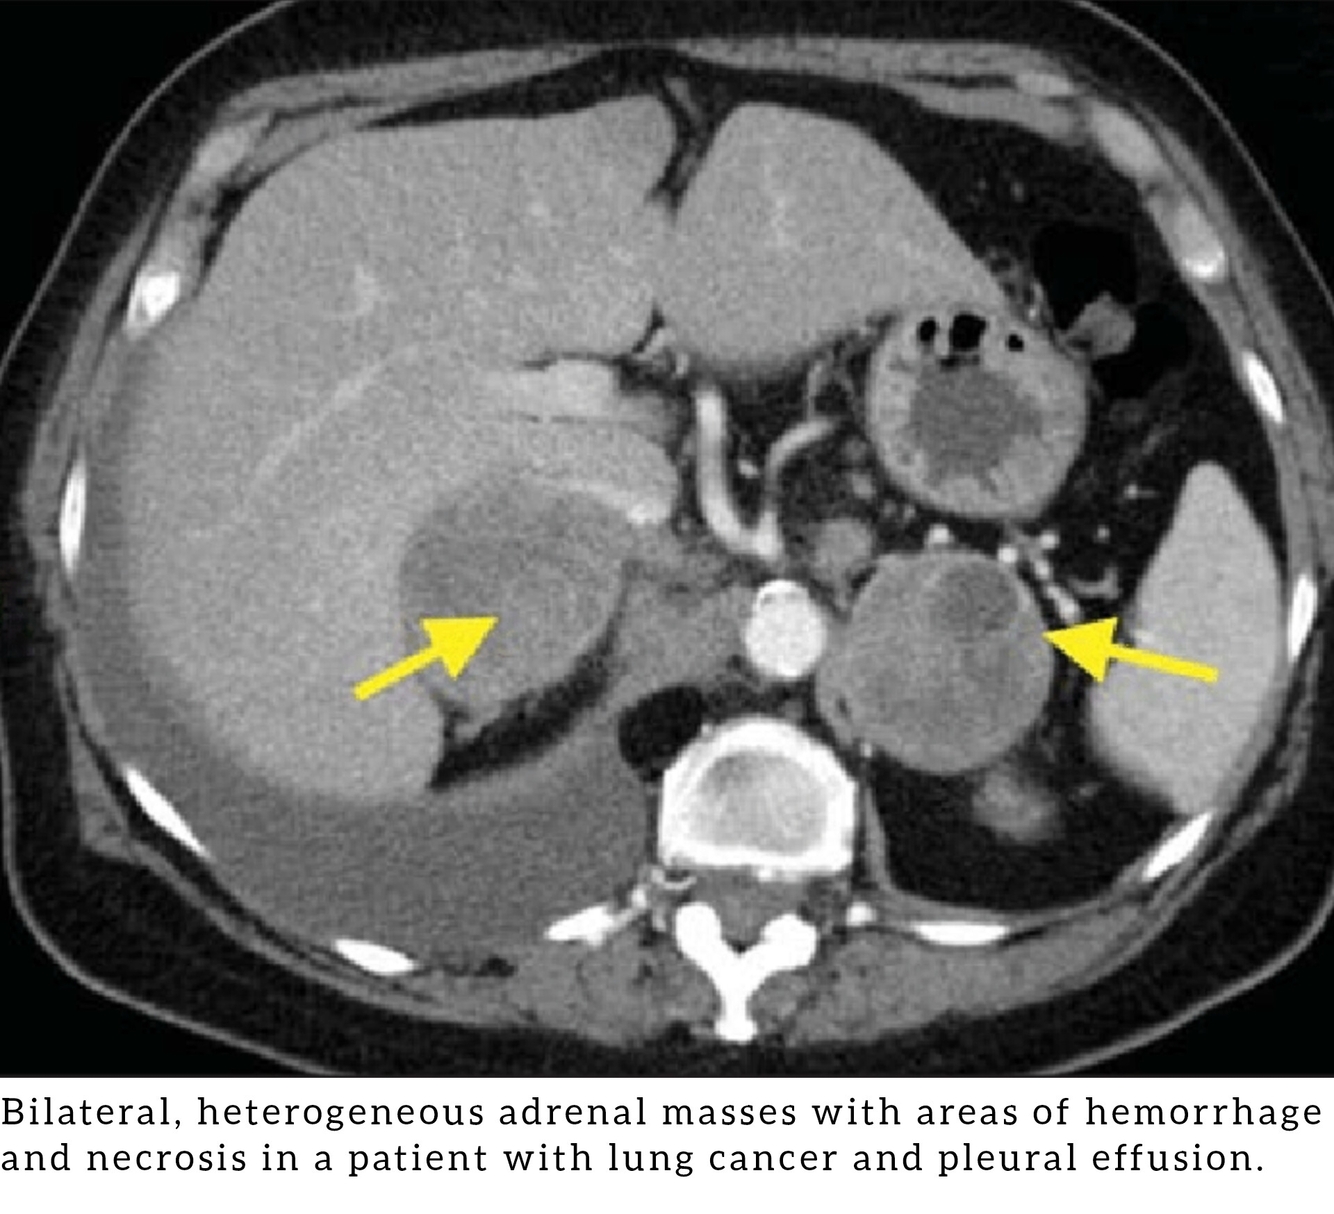

Metástasis suprarrenales.

• Pulmón.

• Mama.

• RCC.

• Melanoma.

• Linfoma.

• Gastrointestinal.

Las metas son la causa más común de masas suprarrenales bilaterales.

DDx: Feocromocitoma, bilateral en un 10% de los casos.